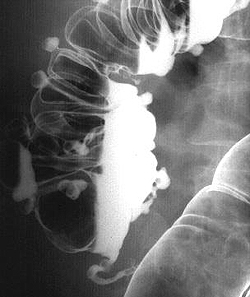

Методы диагностики. Дивертикулез легко выявляется при иригоскопии и при компьютерной томографии (КТ) с контрастированием.

Иригоскопия с двойным контрастированием выявляет дивертикулы (см. рис. 1), любые стриктуры, и может также помочь в обнаружении свищей (см. рис. 2).

Рентгенографическое исследование толстого кишечника с барием (ирригоскопия) позволяет диагностировать дивертикулит, если невозможно проведение колоноскопии, или она дает неоднозначные результаты. Дивертикулы на рентгенографии определяются в виде образований округлой формы, которые имеют диаметр от 0,5 до 5 см. При дивертикулите на рентгенограмме визуализируются одиночные и множественные выпячивания, а края дивертикулов имеют неровные зазубренные контуры. Если на фоне данного патологического состояния происходит перфорация дивертикула с формированием свища, то при проведении рентгенографии свищ будет визуализироваться в виде контрастирующегося тяжа, который распространяется в направлении других органов.

- Рентгенодиагностика. Пациенты с данным заболеванием требуют проведения ирригографии, желательно с двойным контрастированием. На рентгеновском снимке будут видны выпячивания кишечной стенки, сообщающиеся с полостью кишечника. Следует помнить, что при наличии осложнений дивертикулов кишечника сначала необходимо сделать обзорную рентгенографию органов брюшной полости, убедиться в отсутствии признаков перфорации, и лишь затем назначать ирригографию.